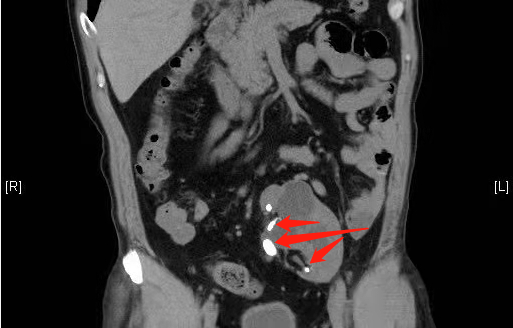

图中箭头处为部分较大结石

挑战远不止于此。患者的肾解剖结构也为异常状态,结构混乱、形状弯曲、分支肾盂等问题,导致多发的结石在左肾内不仅分散而且隐秘难及,仅术前检查,即可见小鸡蛋、鹌鹑蛋大小结石5枚,而黄豆、米粒大小的结石已难以预估,多达数十枚。践行精准医疗,为达成一次性碎石的手术目标,李建兴带领泌尿外科团队反复研究手术方案,最终决定“四镜联合”——超声定位标准经皮肾镜+腹腔镜+电子膀胱软镜+针状肾镜,利用四种微创技术的各自优势,分批分层次碎石。